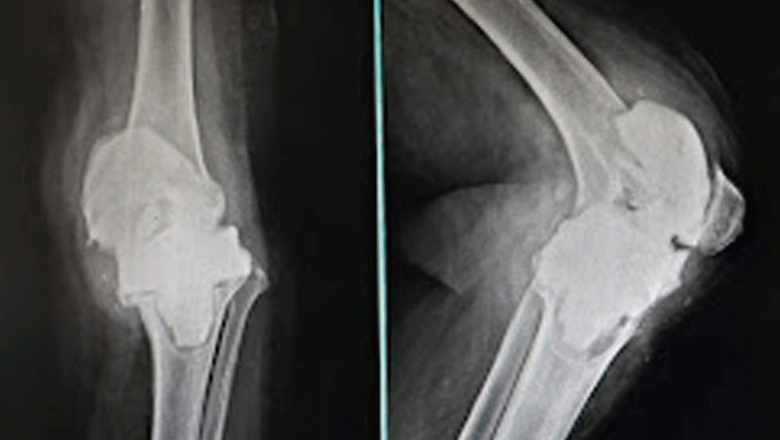

Total Knee Replacement (TKR)

We provide Total Knee Replacement (TKR) using modern implants and less invasive surgical techniques, aimed at reducing recovery time and improving long-term comfort.

Best For:

- Severe knee pain

- Advanced arthritis